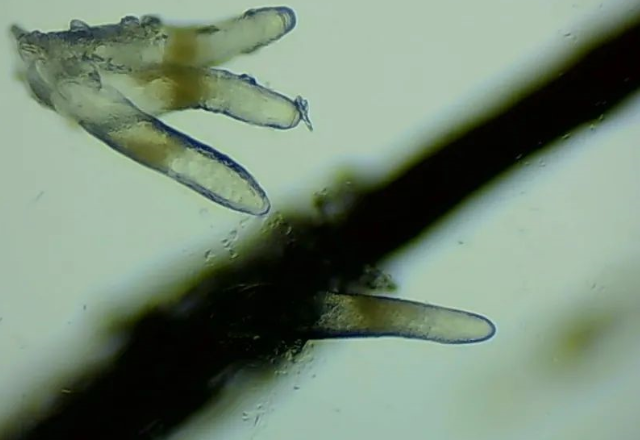

▲顯微鏡下,睫毛上的螨蟲,它們長著透明膠狀的身體,揮舞著爪子。